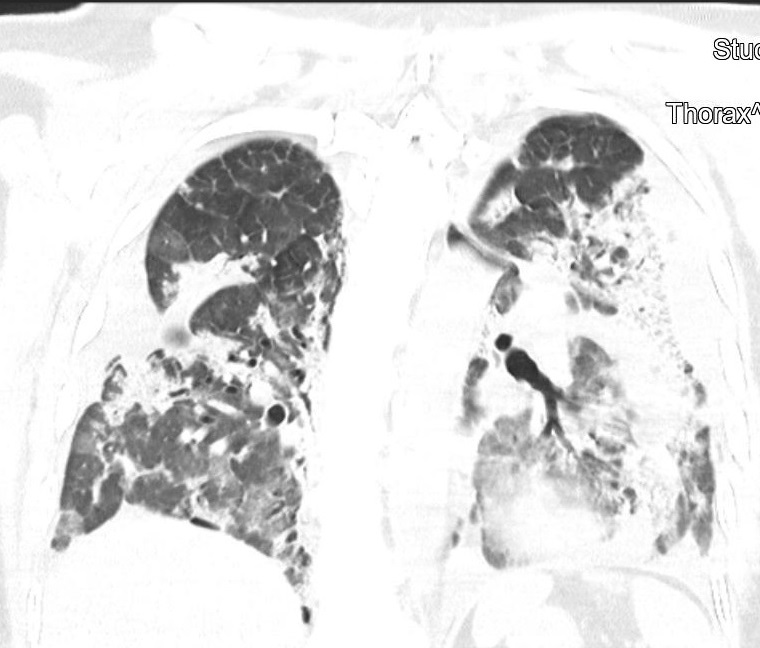

CT snímky vývoje patologických změn na plicích po prodělané nemoci covid-19 u třiapadesátileté doposud zcela zdravé pacientky (fotografie CT nálezu publikovány se svolením Dr. Evy Kočové, Ph.D. – RDG klinika):

Obr. 1: Akutní covid-19 v březnu 2021. Zdravá plicní tkáň je tmavě šedá – prakticky pouze v horních částech obou plic.